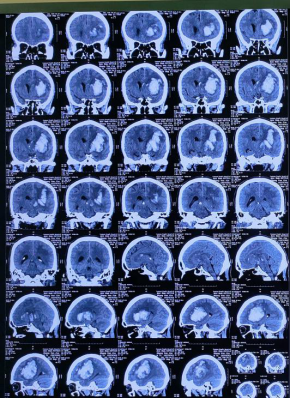

术后复查CT(脑窗)

术后复查CT(骨窗),显示置管位置满意:符合MISTIE3期对于置管位置“优”的定义:长轴置管,管道在血肿横轴的中2/3范围,长轴超过3/4。(“中”:管道接触到血肿,未能满足“优”的要求;“差”:管道未接触到血肿)

9月10日复查CT,显示血肿主体明显缩小,无新增出血。